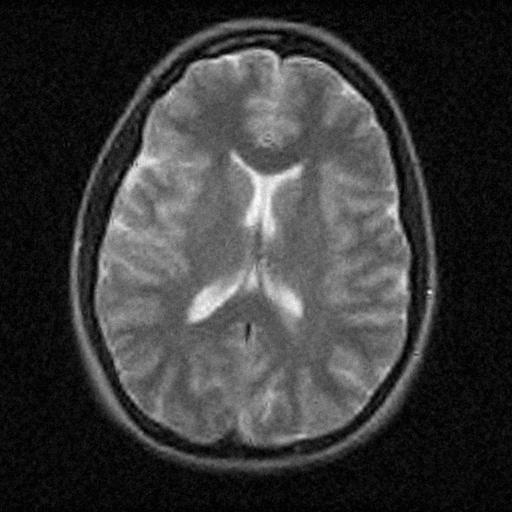

6.3. MR Image reconstruction

The second imaging application is concerned with medical imaging. Following the ideas from [32, 34], we simulate a multi-channel MRI sensing set-up, first using the same sine waves as in the previous experiment (results displayed in Fig 10), and then using spherical beam pattern (see in Fig. 11 for the results). We generate the classical Shep-Logan phantom, and set its dimension to .

The first experiment, depicted in Fig. 10 shows the results obtained by our method when using a Daubechies 4 sparsifying dictionary. Our results are compared to the single sensor analysis, and the results obtained by the Sum-of-Squares recovery [34, 32].

The recovery is obtained from noisy measurements, in which some additive Gaussian noise with variance has been added. The measurements are obtained by subsampling ( samples) of the Fourier transform. We see here that the fused compressed sensing is better capable of handling a multi-channel problem with unusual illumination (compared to the Sum-of-Squares method). Moreover, more details are preserved, when compared to the single sensor analysis method.

Some noise still appears in the image, but can easily be thresholded further if needed. One important aspect of MR Images that hasn’t been considered in this research, is the fact that they are sparse in gradient. One usually prefers to minimize the Total Variation instead of the norm or another frame using analysis.

Although we have not explicitly written the theory here, the recovered images in Fig. 11 show the results when using a TV minimization instead of the analysis.

| analysis | Sum of Square fusion | Fused analysis | |

|---|---|---|---|

| SSIM | |||

| PSNR | |||

| error |